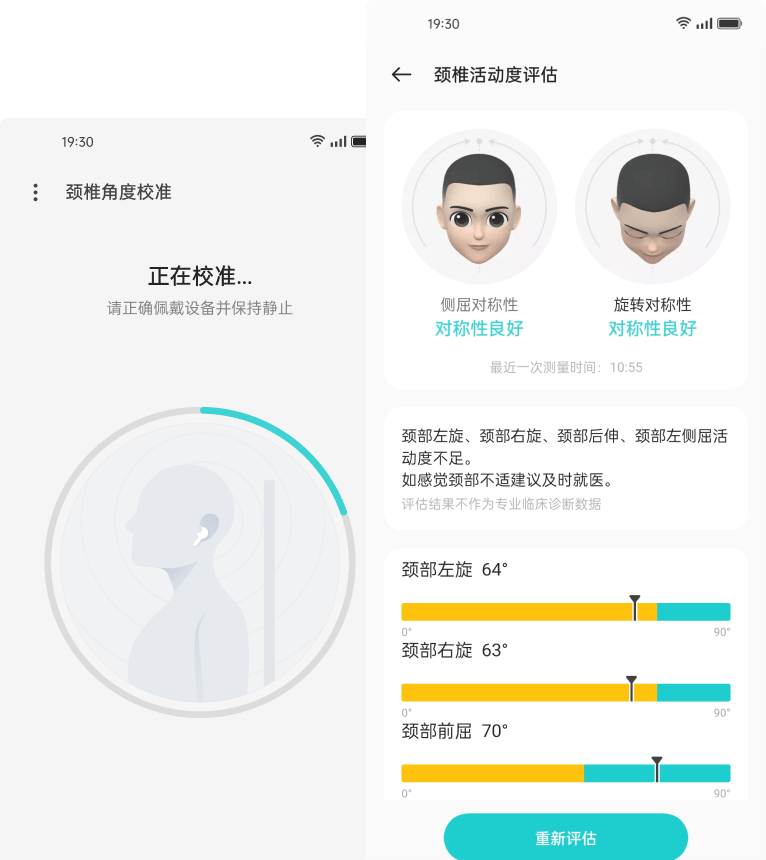

Личный врач⁵шейного отделаOnePlus Buds Pro 2 автоматически определяет положение головы и шеи, создаёт отчёт. 3-минутный тест позволит Вам оценить активность шейного отдела.Не просто тестирование. Мы сотрудничаем с врачами-реабилитологами Пекинского института спорта, чтобы создать программу упражнений для снижения нагрузки шейного отдела.

5. Функция здоровья шейного отдела позвоночника поддерживается ColorOS 11.0. Для использования функции здоровья шейного отдела обновите прошивку до последней версии. 3-минутное время тестирования может варьироваться в зависимости от индивидуальных особенностей пользователя.